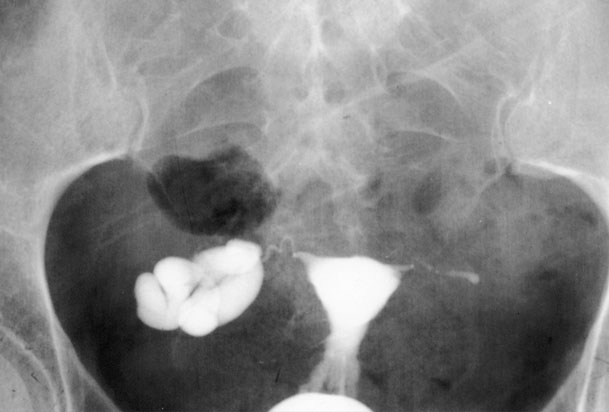

در صورت انسداد لوله های رحمی و یا وجود چسبندگی رحم، شانس باروری کاهش می یابد. در این روش با استفاده از اشعه X و ماده حاجب چسبندگی های درون رحمی، پولیپ، فیبروم و دیگر مشکلاتی که سبب انسداد لوله ها و جلوگیری از لقاح تخمک و اسپرم می گردد قابل تشخیص است.

به طور طبیعی ماده حاجب باید رحم و لوله های رحمی را پر نماید یعنی هنگامی که در رحم و لوله ها هیچگونه انسداد و مشکلی وجود نداشته باشد.

ماده حاجب بعد از تزریق فضای داخل رحم و لوله ها را به طور یکنواخت پر خواهد کرد ولی در صورت انسداد ماده حاجب نمی تواند فضای داخل رحم و لوله ها را پر کند. بعد از تزریق از رحم عکسبرداری می شود.